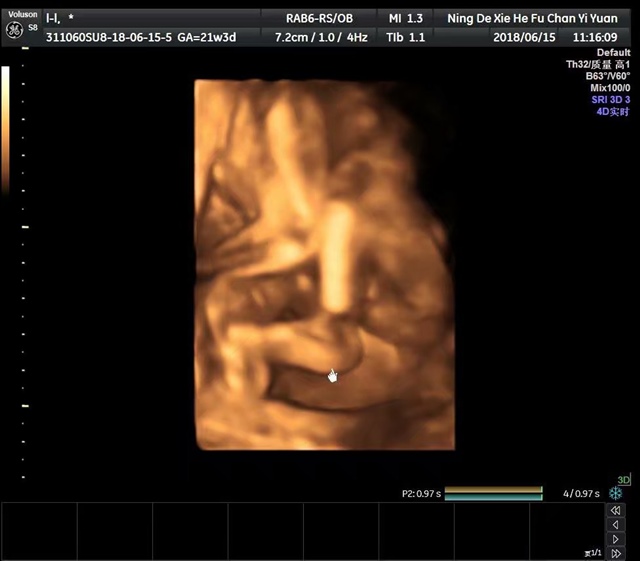

孕23周+0天

是男孩子吗